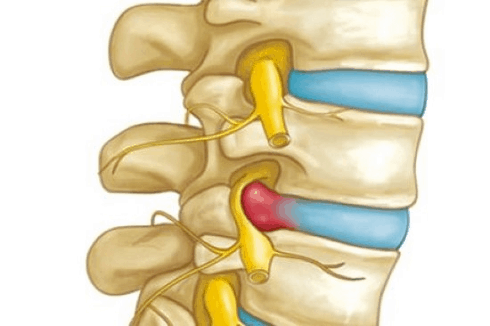

When people say you have a spinal disc bulge, it primarily refers to a bulging out of the disc, or the lava-cake after prolonged periods of time under weight, or through repeated movements in the spine (typically bending forwards). These factors lead to a bulging out of the gooey content of the disc beyond where it would normally be contained. This may lead to other nearby structures getting squished and compressed, resulting in pain which increases in intensity with certain movements (particularly bending forwards), including numbness or pins and needles depending on where the bulge has occurred.